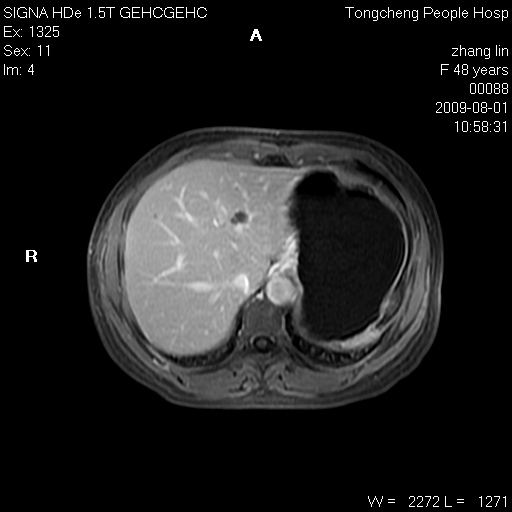

女,48岁。健康体检,彩超发现右肾占位性病变。平素健康。

临床诊断:右肾占位性病变,性质待定(囊肿?肿瘤?)。

上中腹部mr平扫+增强扫描,图像如下:

右肾上极见一类圆形病灶,t1wi呈等信号t2wi呈等高混杂信号,三期增强无强化,边界清---考虑囊肿出血。

同反相位均表现为等信号,病变无强化,考虑含蛋白的囊肿可能,弥散加权相或许有些帮助,